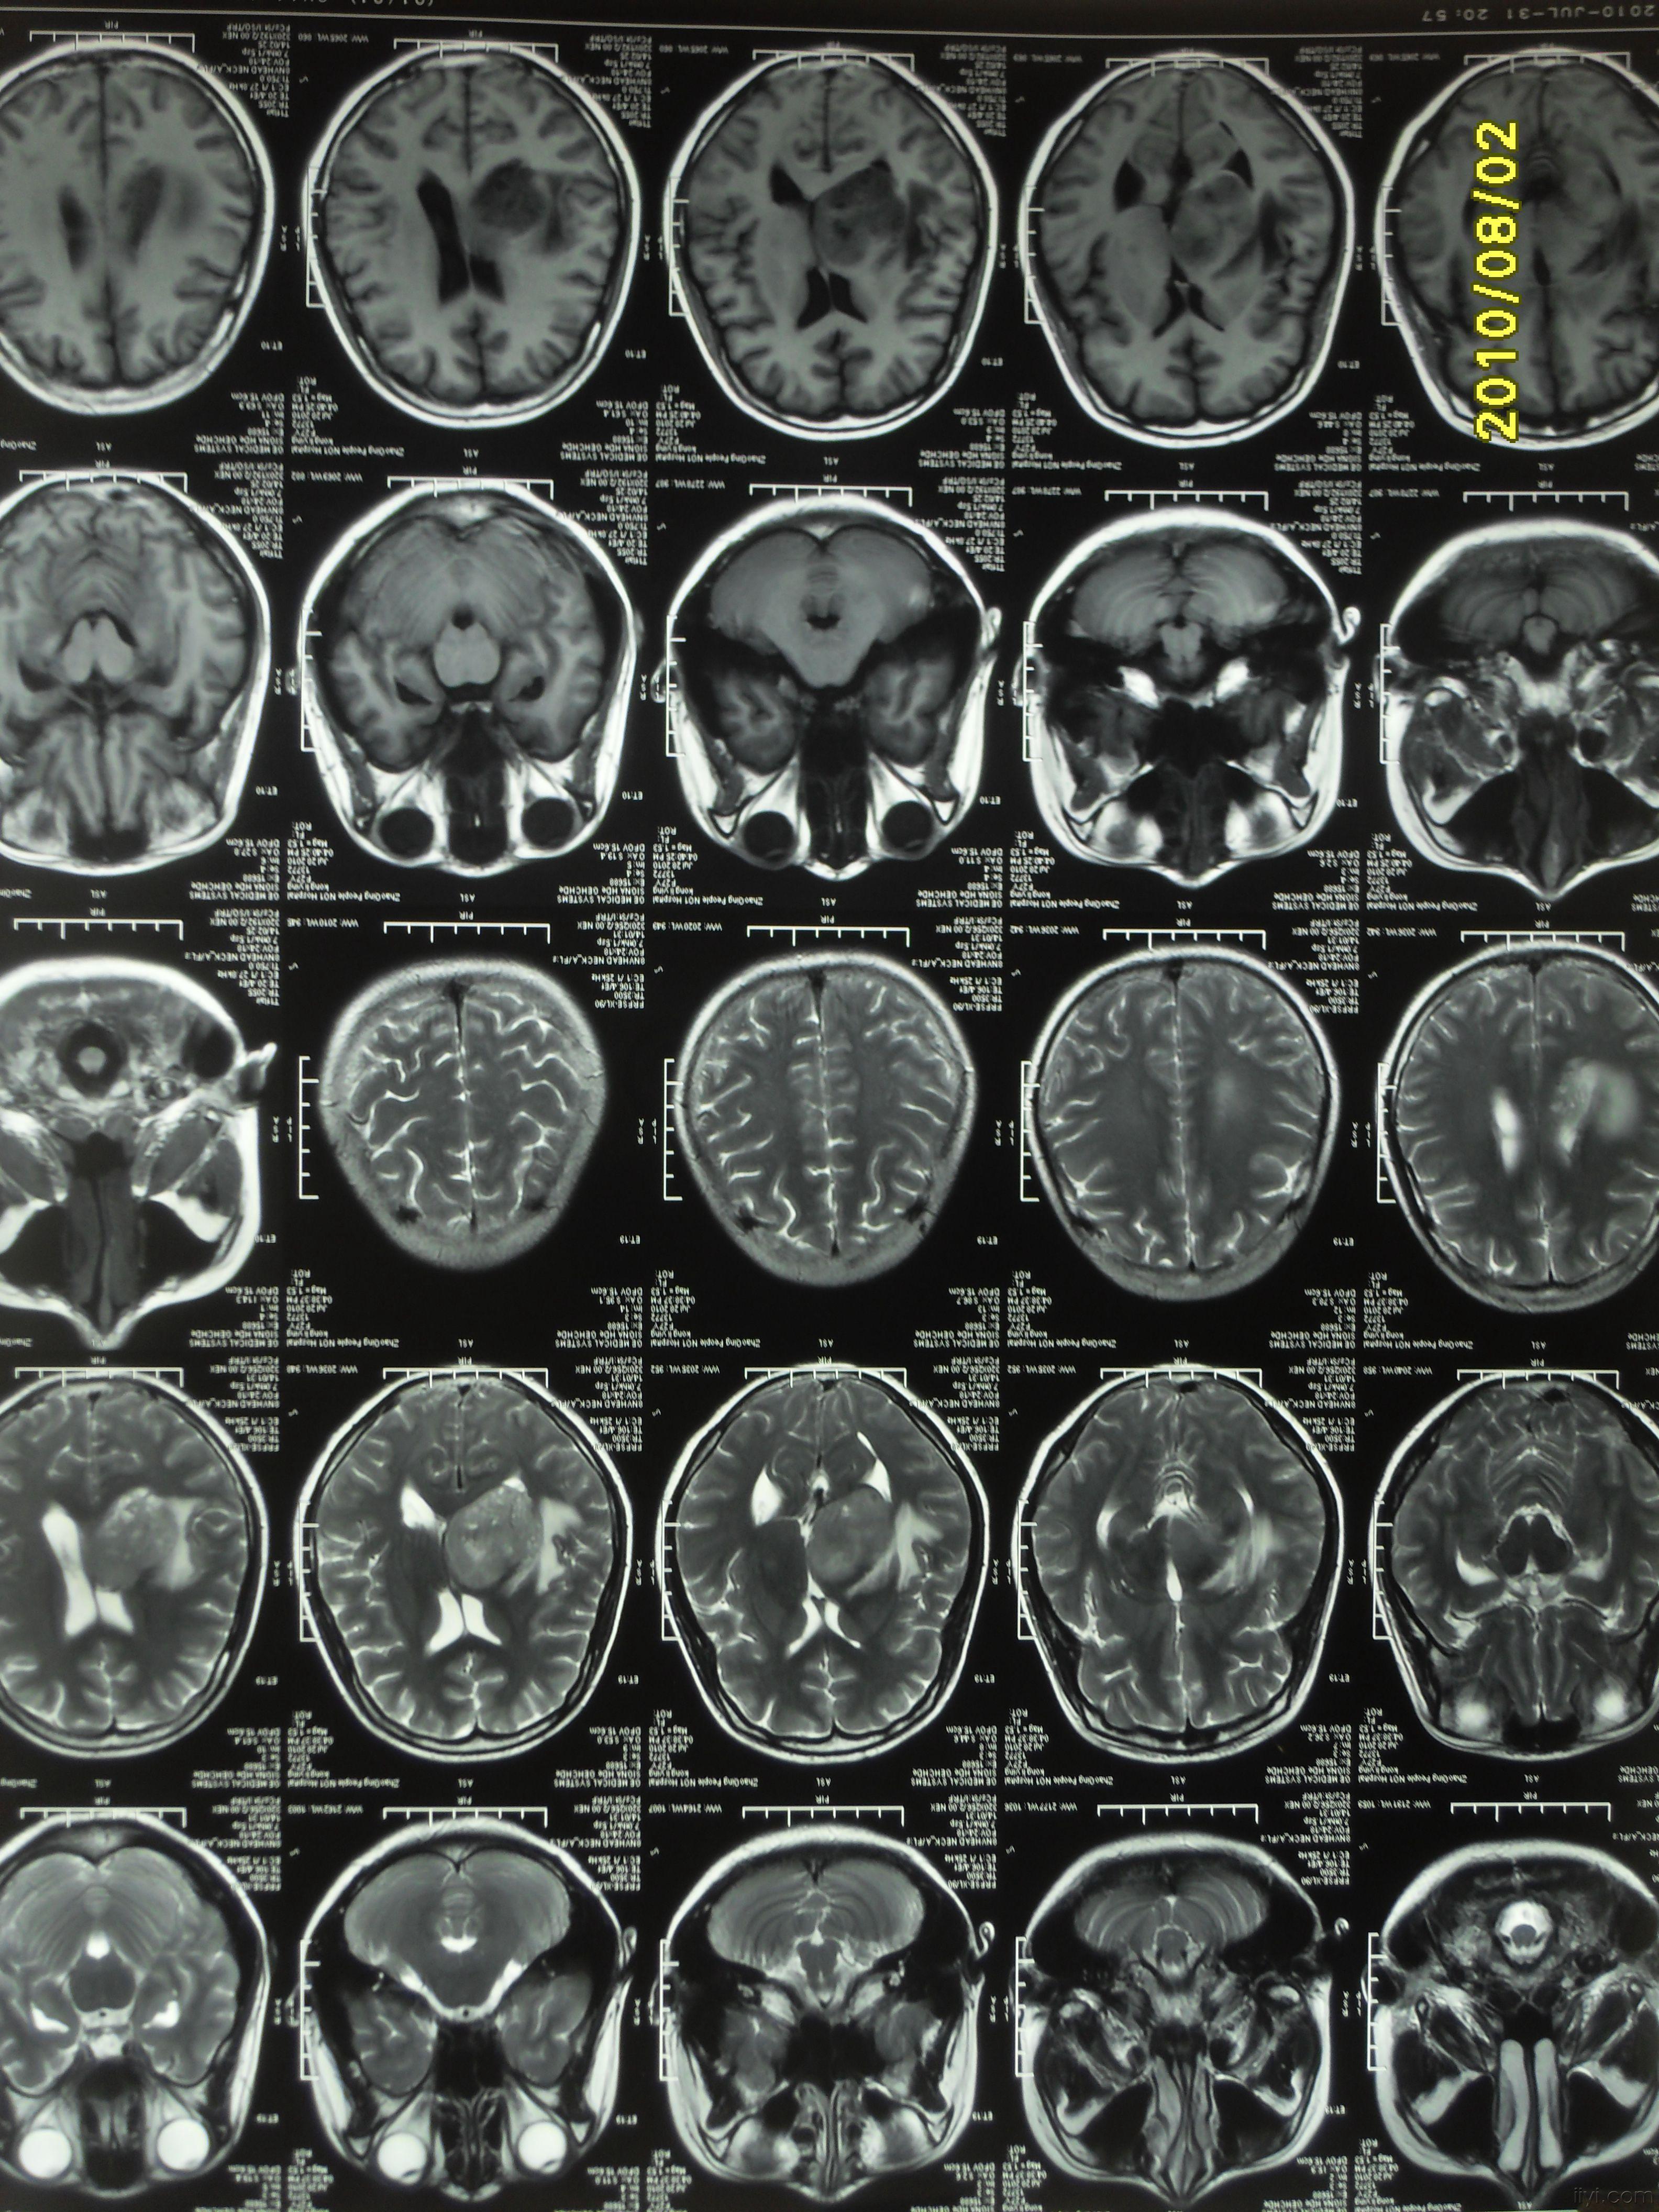

脑胶质瘤影像学及鉴别诊断